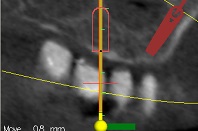

עקב חוסר בעצם ואי רצון מצד המטופל לעבור הרמות סינוס בוצע תיכנון ממוחשב של מיקום השתלים עוד בטרם ההשתלה.

ההשתלות בוצעו דרך שבלונה שהוכנה במדפסת תלת מימד בהתאם לקובץ הממוחשב.